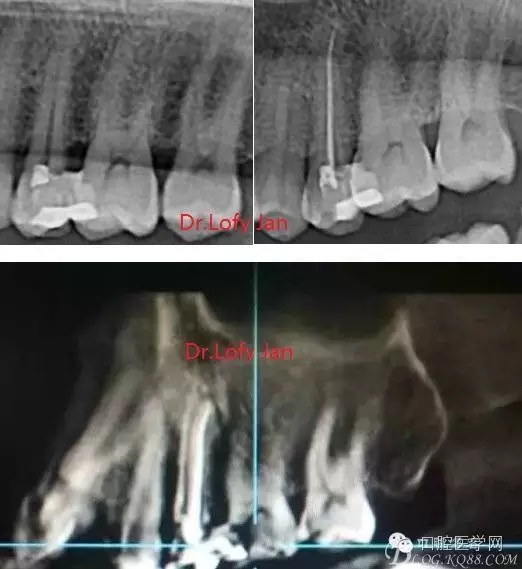

前言:自己做的一些曲面斷層片在未試尖根管治療中的病例整理,發(fā)現(xiàn)問題很多包括自身的,技術(shù)的,還有設(shè)備的問題,予以總結(jié)整理并期待進(jìn)一步提高。

《數(shù)字化根尖片、曲面斷層片、CBCT測量牙齒長度準(zhǔn)確性的比較研究》文中顯示:平行投照數(shù)字化根尖片影像長度和牙齒實際長度之間無顯著性差異(P0.05);數(shù)字化曲面斷層片影像長度和牙齒實際長度之間有顯著性差異(P0.05),平均失真率為17.05%。CBCT冠狀面測量結(jié)果中除上頜前磨牙區(qū)、下頜前磨牙區(qū)與真實長度差異無統(tǒng)計學(xué)意義(P0.05)外,其余6個分區(qū)差異均有統(tǒng)計學(xué)意義(P0.05);矢狀面測量結(jié)果中上頜磨牙區(qū)、下頜磨牙區(qū)、下頜前磨牙區(qū)、下頜尖牙區(qū)、下頜前牙區(qū)與真實長度比較差異均有統(tǒng)計學(xué)意義(P0.05)。結(jié)論平行投照數(shù)字化根尖片較曲面斷層片和CBCT能更加精確地反映牙齒的真實長度。

病例分析:曲面斷層片在x線輔助診斷與檢查中目前大多數(shù)文獻(xiàn)和著作都建議只能作為初診拍片檢查手段,不能作為終末疾病的確診與手術(shù)療效的評價指標(biāo),臨床大部分中小型門診都因為設(shè)備不齊全導(dǎo)致信息偏差很大。